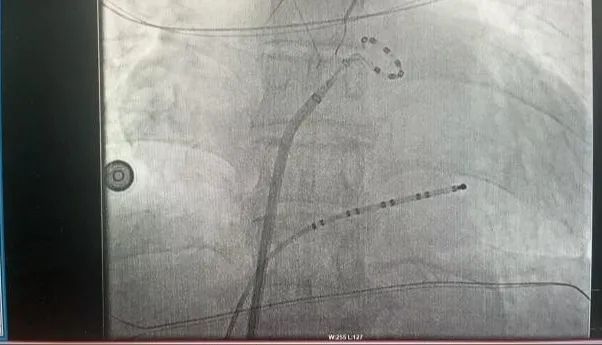

此次手术患者均为持续性房颤患者,由延安大学咸阳医院吴栋梁院长、心律失常专家刘雄涛副院长带领介入团队开展,安全高效、圆满完成手术,手术过程患者全程清醒,术中自诉感觉良好,无痛苦感受。术后患者的心律恢复并维持了窦律,目前恢复情况良好,无任何并发症出现。